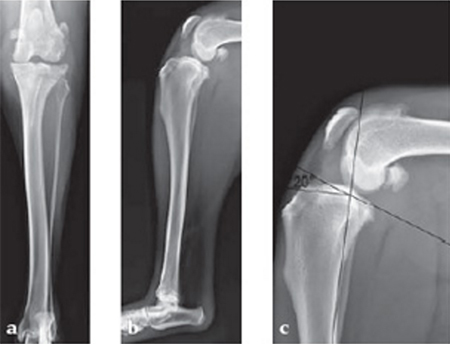

Case 1: Two-year-old Labrador Retriever

2-years-old Labrador Retriever, 30 kg, female. Chronic lameness in both hind limbs, chronic bilateral cranial cruciate ligament tears, with subsequent stifle joint instability and degenerative joint disease. At that time, she was more clinically lame on the left hind limb, and a surgical correction was subsequently performed on this limb. X-rays of the stifle joint revealed the degenerative joint changes and an effusion; the tibial plateau slope was 20. In addition, the x-rays confirmed that there was a slight amount of tibial torsion that also was observed clinically, accounting for a slight internal rotation of the distal limb. Radiographically, this could be assessed by a 4 mm shift of the normal point of intersection of the medial aspect of the calcaneus with the deepest point of the talar sulcus.

The stifle joint was surgically explored. All remaining remnants of the torn cranial cruciate ligament were debrided; in addition, the caudal pole of the medial meniscus was torn/crushed, and a partial meniscectomy of the damaged portion was performed. A TPLO plate 3.5 was applied to stabilize the fracture. The plate was applied in a neutral fashion. Postoperative x-rays revealed a tibial plateau angle of 5, and a correction of the torsion to 0 mm.

Follow-up x-rays at 8 weeks postoperatively revealed that the osteotomy had healed, and the dog was doing very well. The identical procedure was performed on the opposite stifle joint 2 months later. Healing was again obtained 8 weeks postoperative. Presently, the dog is about 1 year postoperatively and functioning very well.